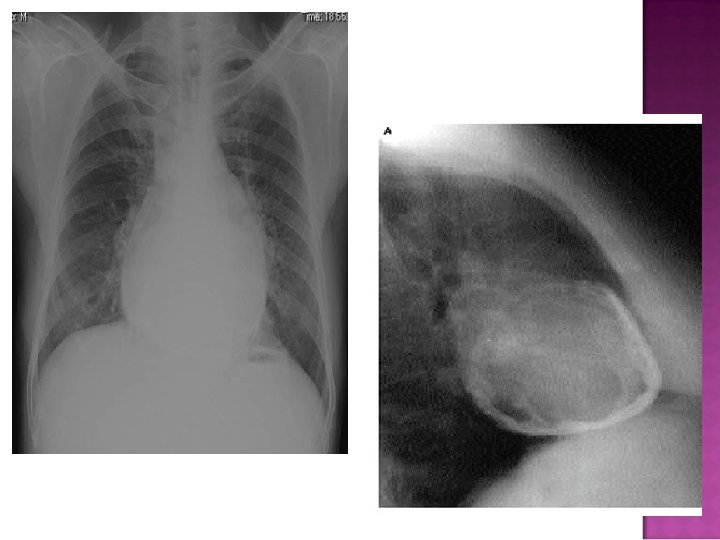

Cardiomegaly due to a massive pericardial effusion. At least 200 m. L of pericardial fluid must accumulate before the cardiac silhouette enlarges.

Sudden inc in size of cardiac silhouette w/o specific chamber enlargement Effacement of the normal cardiac borders Development of a “flask” or “H 2 O-bottle” shaped heart

May have (+) fat pad sign Separation of mediastinal / retrosternal fat and epicardial fat by > 2 mm

Normal in patients with acute pericarditis unless pericardial effusion is present Enlarged cardiac silhouette Requires 200 cc of fluid